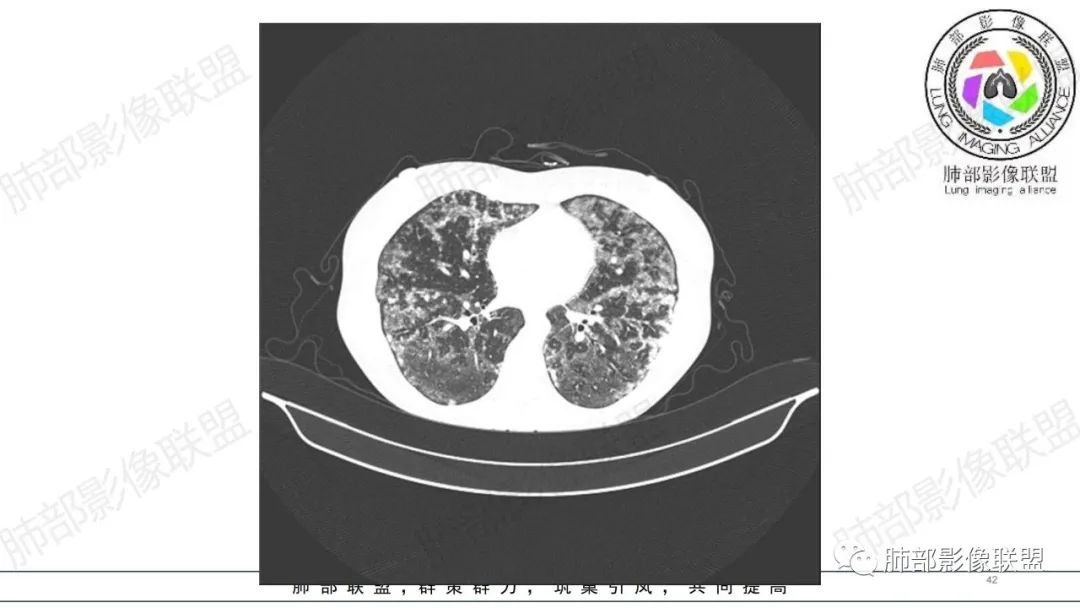

34岁女性患者,“哮喘”病史30年,近期有可疑刺激性气体吸入史;因乏力半年,咳嗽、憋气、发热4天就诊;6.1CT提示双肺广泛毛玻璃影及粟粒样结节,胸膜下闲置及血管周闲置,可见树丫征,部分小叶间隔增厚。考虑:1.过敏性肺泡炎,有可疑刺激气体接触史,胸膜下闲置,广泛毛玻璃影,地图样分布,粟粒结节边界模糊,支持过敏性肺泡炎,但糖皮激素治疗效果不佳,且动态复查血常规血红蛋白进行性降低,过敏性肺泡炎 不符合;2.肺含铁血黄素沉积症:患者30“哮喘”病史,可能为肺含铁症状,肺部CT提示双肺弥漫毛玻璃影及粟粒结节影,中下肺明显,肺底部分小叶间隔增厚,近期咳嗽、憋气、发热,血常规血红蛋白进行性下降,考虑肺含铁急性期症状,但临床无咯血症状,肺含铁不典型。综合考虑:肺含铁血黄素沉积症>过敏性肺泡炎。

年轻女性 ,急性喘息发热,肺部影像弥漫磨玻璃密度,部分细小腺泡结节,胸膜下黑线显示,短期复查,病变密度增高,下肺明显,血管周围肺组织累及较少、且逐渐成小叶间隔分布。考虑弥漫肺泡内病变,并经淋巴道转移,下肺比上肺明显,多为免疫细胞功能下肺较强。1.过敏性肺泡炎,有相关病史,三层密度特点、头尾测分布,符合。2 肺泡微石症,多有钙化,且缓慢起病,病程不太符合,放待排。3 吸入相关肺损伤,有病史,疾病演变过程也符合渗出-肉芽肿改变,建议详细询问病史。4 感染性病变,结核?病变气道分布为主,如此弥漫且没有树丫不符合。5.巨细胞病毒,可以磨玻璃 结节 改变,没有免疫缺陷病史。最后考虑吸入所致 1过敏性肺泡炎、吸入性肺损伤 鉴别肺泡微石症。

肺内气腔磨玻璃结节,肝脾肿大,治疗后间质改变,弥漫大B可能